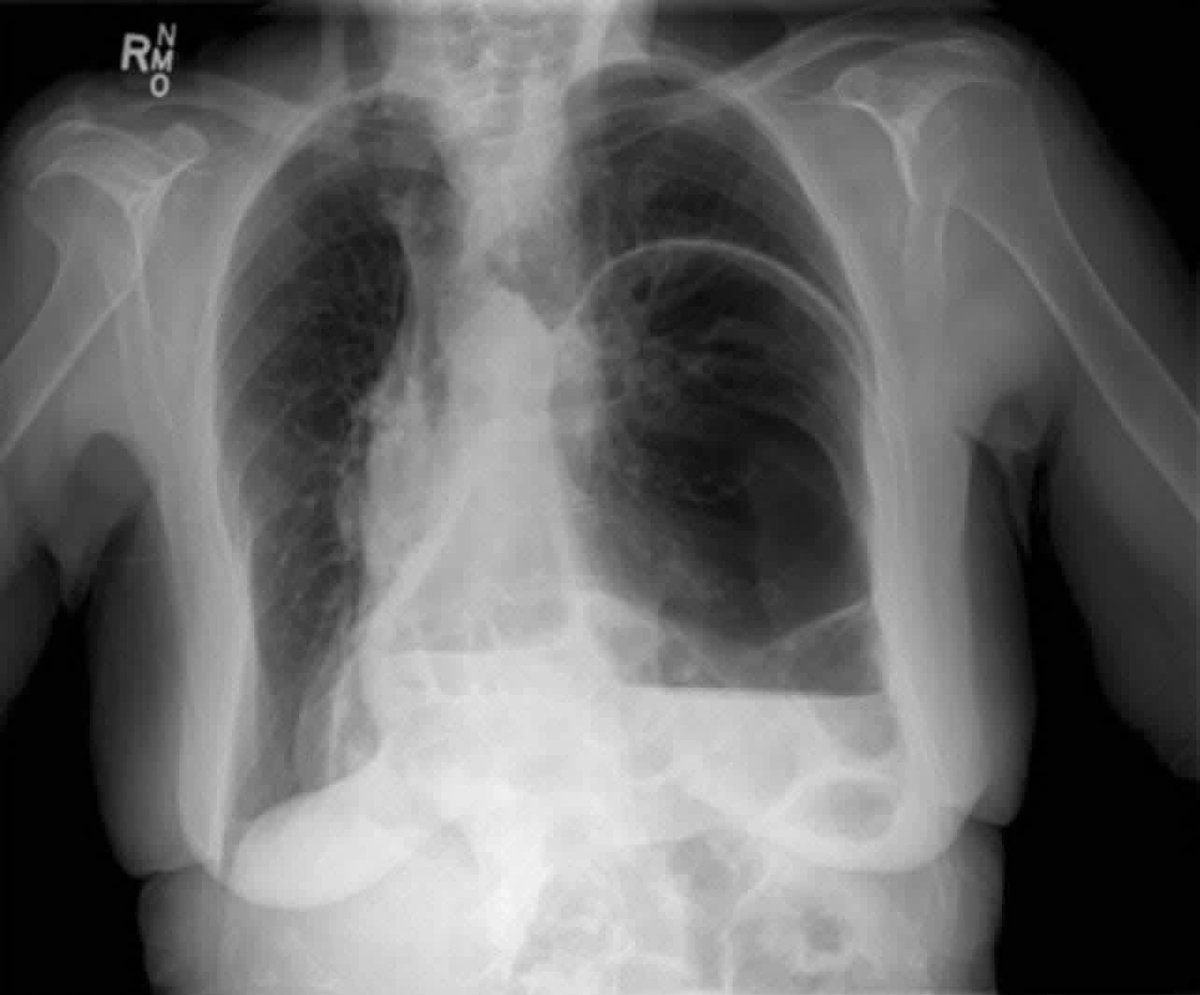

CXR of a patient presenting with vomiting and shortness of breath.

What is the diagnosis?

Xray findings?!